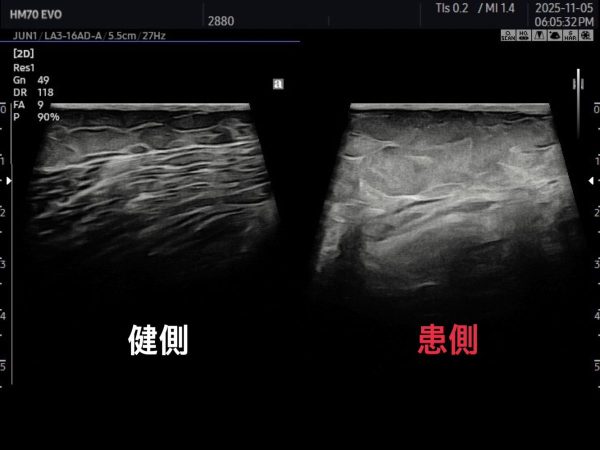

左は筋線維が均等になっているのに対して

右は筋線維の連続性がなくなっているため

エコー所見にて

大内転筋付着部の肉離れ1度~2度になりかけている所見となります。